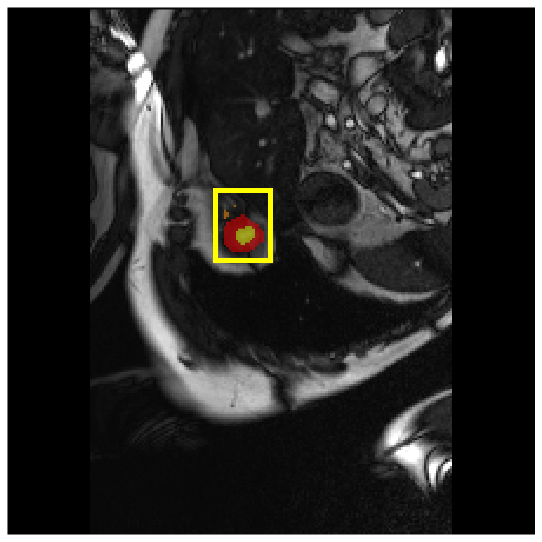

Medical image segmentation plays a critical role in various diagnostic workflows, as it enables accurate delineation of anatomical structures and pathological regions, thereby enhancing disease interpretation, treatment planning, and outcome prediction. Jang et al. [1] has demonstrated that improved segmentation performance can lead directly to reduced diagnostic error rates and increased clinician confidence. Building on the remarkable success of deep learning across diverse domains [2, 3, 4, 5], recent progress in medical image segmentation has been primarily driven by deep learning. Since the introduction of U-Net [6], segmentation methods have rapidly evolved, with convolutional neural networks (CNN)-based models [7, 8, 9] and Transformer-based models [10, 11, 12] showing superior performance in computed tomography (CT) and magnetic resonance imaging (MRI) segmentation. However, various challenges such as blurriness, noise, and low contrast often hinder the accurate diagnosis of diseases. Applying various image enhancement techniques to generate an enhanced image from the input can alleviate this problem, as existing methods have demonstrated improved segmentation accuracy [13, 14, 15]. Nevertheless, input images may unintentionally lose crucial information contained in the original image during enhancement. As a result, the segmentation model suffers from performance degradation (Fig. 1(a) and (b)). Therefore, we argue that it is crucial to leverage the advantages of both the original and enhanced images through image fusion strategies.

4.3.2 Visual Comparisons

Visualization of our method on the Synapse and ACDC datasets is shown in Fig. 3(a) and Fig. 3(b). For the Synapse dataset illustrated in Fig. 3(a), FCT failed to accurately segment SM and GB, while MERIT achieved precise segmentation of SM but struggled with GB. In contrast, our method achieved accurate segmentation of both SM and GB. Regarding the ACDC dataset shown in Fig. 3(b), while previous methods achieve comparable segmentation of the Myo and LV to the GT, they exhibit noticeable errors on the RV, including invasion into adjacent organs and misrecognition. On the other hand, our method accurately segments across all three structures Myo, LV, and RV, performing as precisely as the GT. We demonstrate the superiority of our method quantitatively and qualitatively.